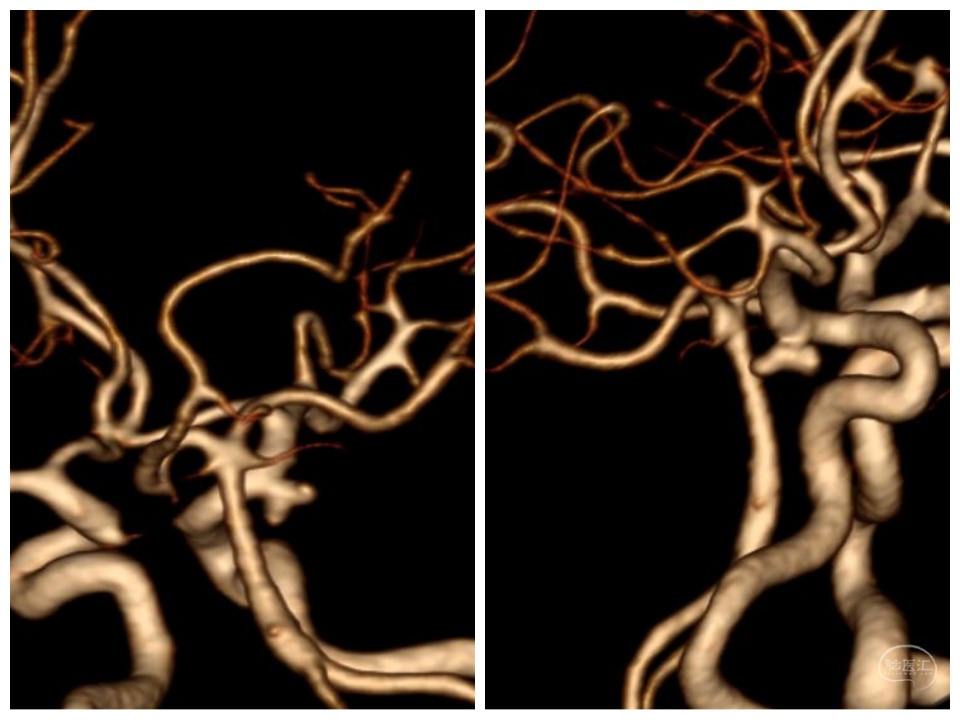

正侧位

三维

其他血管情况